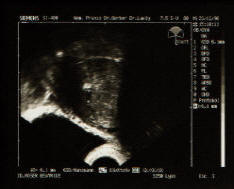

23.12.98

Das Erste Photo von mir.

Da bin ich gerade 6.1mm gross